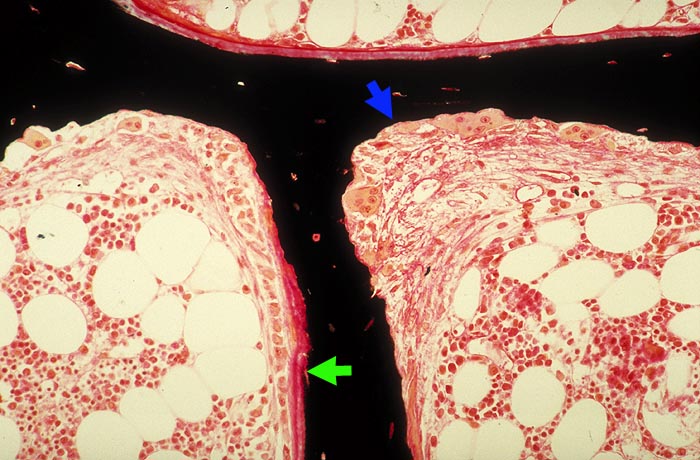

Renale Osteopathie

Knochen, Knorpel, Gelenke

Knochen

Knochen (Wirbelkörper und Discus intervertebralis)